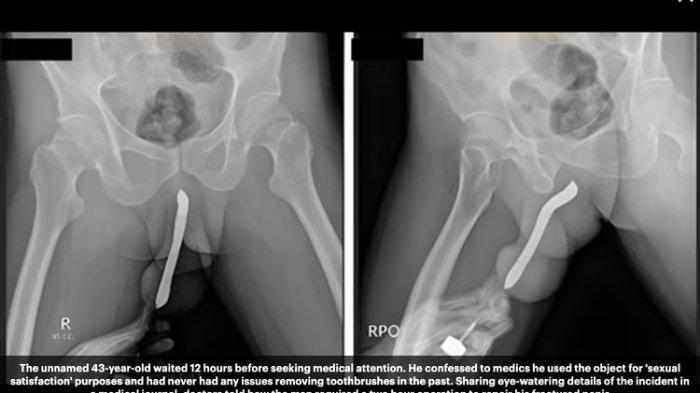

Tepatnya, pria berusia 43 tahun itu datang ke rumah sakit pemerintah di Jawa Timur 12 jam setelah kejadian.

Ia mengatakan memasukkan sikat gigi di penisnya untuk 'kepuasan seksualnya'.

Dikutip dari Daily Mail (1/3/2024), kejadian pria memasukkan sikat gigi ke penis dan patah saat berhubungan seks itu disebutkan dalam International Journal of Surgery Case Reports yang terbit Maret 2024.

Dalam jurnal tersebut disebutkan, pasien mengalami cedera penis saat melakukan hubungan seksual dengan posisi wanita di atas pada malam sebelumnya.

Waktu sejak kecelakaan sampai dia datang ke ruang gawat darurat rumah sakit untuk meminta pertolongan sekitar 12 jam.

Pria tersebut melaporkan penisnya melengkung, nyeri, dan bengkak.

"Dia memiliki riwayat memasukkan sikat gigi ke bagian punggung dan perut penisnya melalui sayatan kecil di rumahnya pada tahun 2017 untuk kepuasan seksual.

Oleh karena itu, pasien telah menyimpan alat tersebut di penisnya selama enam tahun," tulis laporan jurnal tersebut.

Akibat cedera tersebut, pasien harus menjalani operasi yang dilakukan oleh seorang ahli urologi dengan spesialisasi trauma dan rekonstruksi.

Dokter yang menangani pasien mengatakan, salah satu kesulitan operasi pada kasus ini adalah ketika melepaskan sikat gigi yang terlanjur menempel pada jaringan di sekitarnya.

Operasi dilakukan selama dua jam dengan total volume kehilangan darah kurang lebih sebanyak 100–150 mililiter.